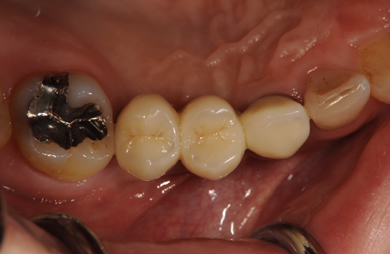

| 性別/年齢 | 男性 / 29歳 | ||||||||||||||||||||||||||||||||

| 主訴 | 右上の歯のない部分に歯を入れたい。 | ||||||||||||||||||||||||||||||||

| 治療内容 | インプラント3本(ソケットリフト+GBR)、ハイブリッドセラミック3本 | ||||||||||||||||||||||||||||||||

| 総治療費 | 1,264,800円 | ||||||||||||||||||||||||||||||||

| 治療期間 | 7ヶ月 |